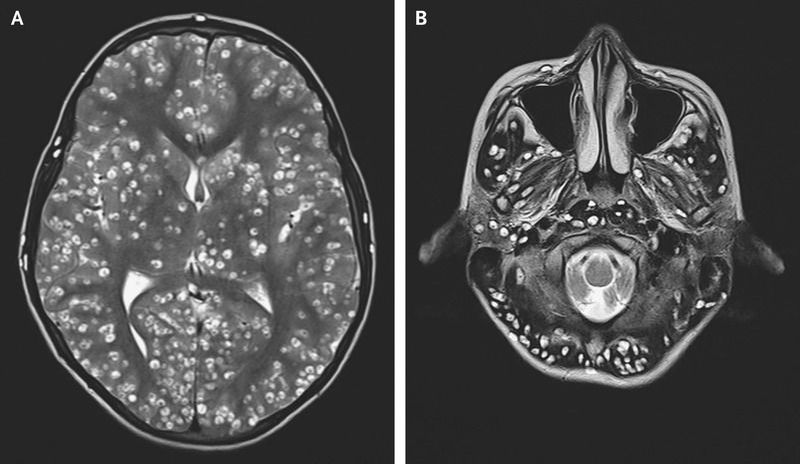

An 18-year-old man presented to the emergency department with generalized tonic–clonic seizures. His parents reported that he had been having pain in the right groin for 1 week. On physical examination, the patient was confused. He had swelling over the right eye and tenderness in the right testis. Magnetic resonance imaging of the head showed numerous well-defined cystic lesions throughout the cerebral cortex (Panel A) and the brain stem and cerebellum (Panel B) that were consistent with neurocysticercosis. Well-defined cysts that contained echogenic nodules were seen on ultrasonography of the eye and the right testis. Western blot analysis and enzyme-linked immunosorbent assay showed positive results for serum cysticercosis IgG antibody. In the context of high cyst burden, treatment with antiparasitic medications can worsen inflammation and cerebral edema, and in the presence of ocular lesions, inflammation can lead to loss of vision. Therefore, antiparasitic medications were not administered in this case. Despite treatment with dexamethasone and antiepileptic medications, the patient died 2 weeks later.